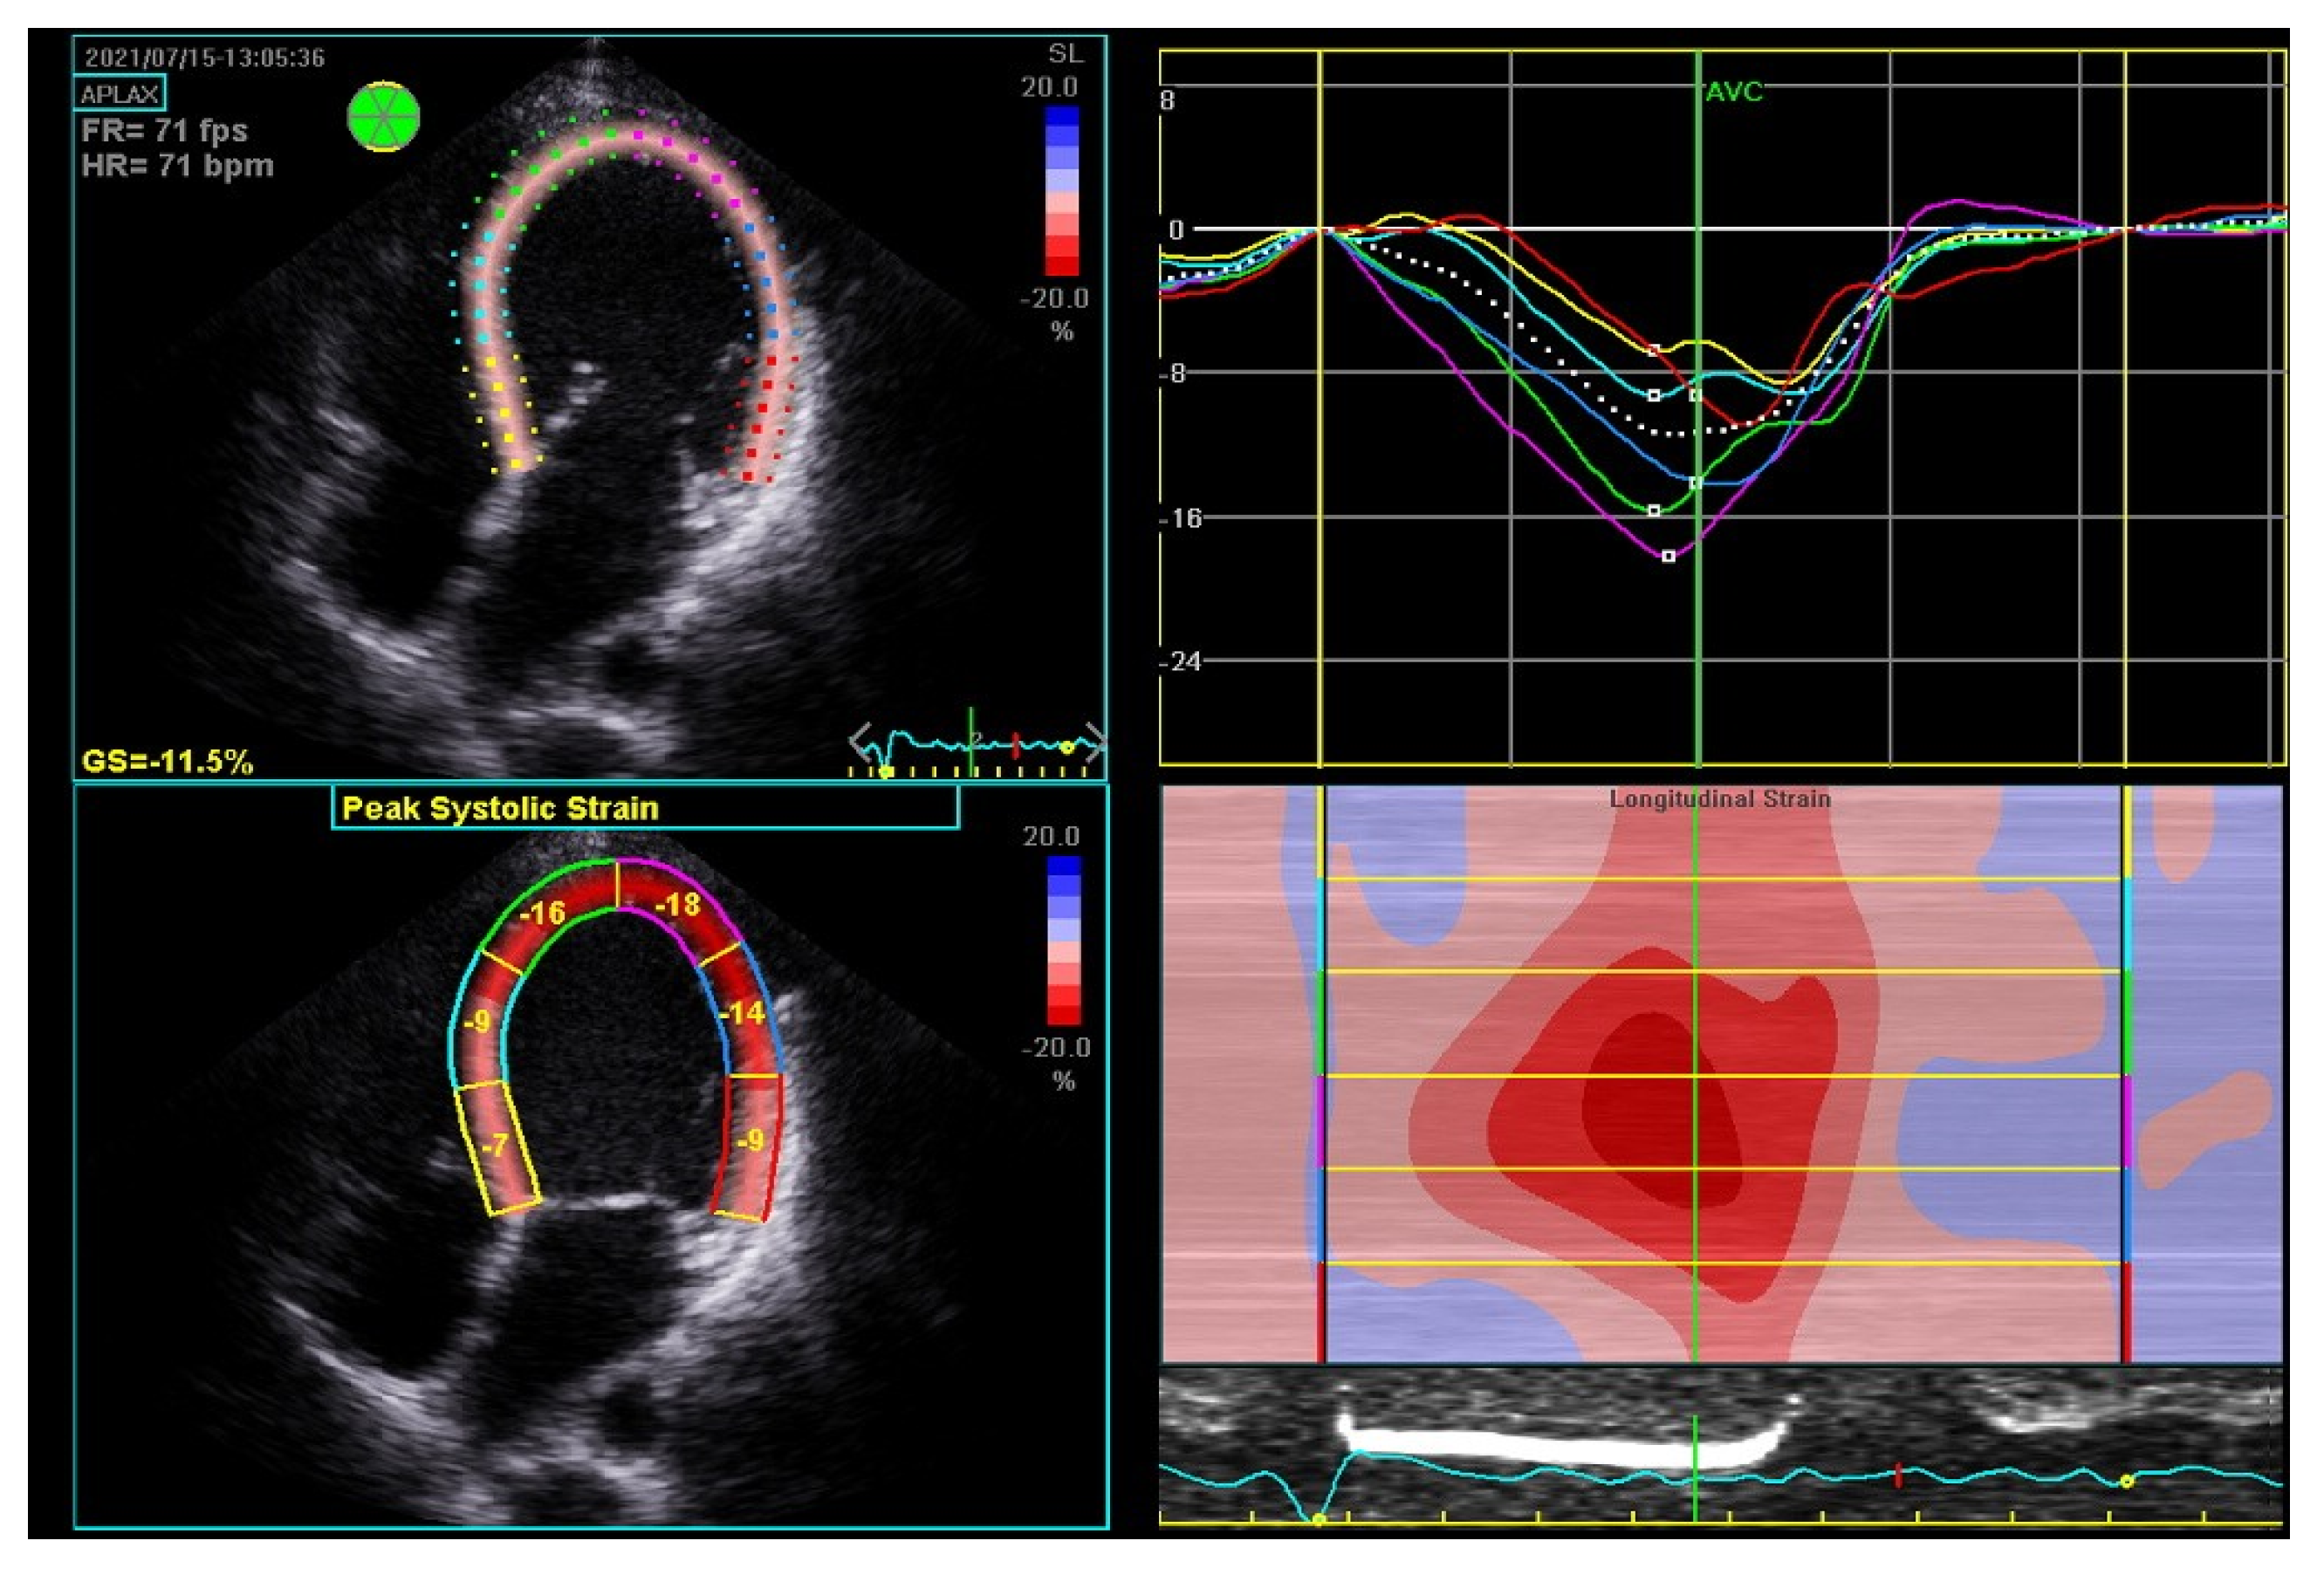

- Sugahara, M.; Kagiyama, N.; Hasselberg, N.E.; Blauwet, L.A.; Briller, J.; Cooper, L.; Fett, J.D.; Hsich, E.; Wells, G.; McNamara, D.; et al. Global Left Ventricular Strain at Presentation is Associated with Subsequent Recovery in Patients with Peripartum Cardiomyopathy. J. Am. Soc. Echocardiogr. 2019, 32, 1565–1573. [Google Scholar] [CrossRef]